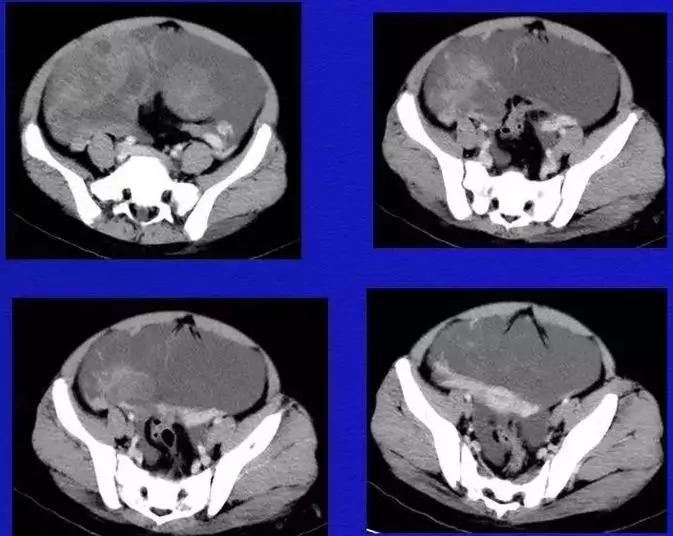

病理:卵巢子宫内膜样癌

病例10

女,39 岁,体检发现盆腔肿块1月余

CA125:51U/ml

病理:左侧卵巢卵泡膜-纤维瘤